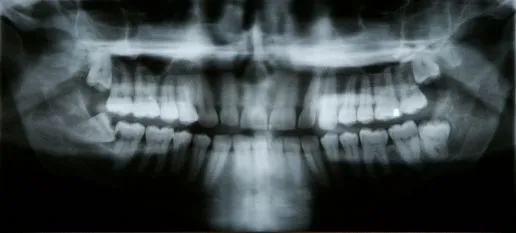

Panoramic dental X-ray image reviewed at Valdosta GA dental practice.